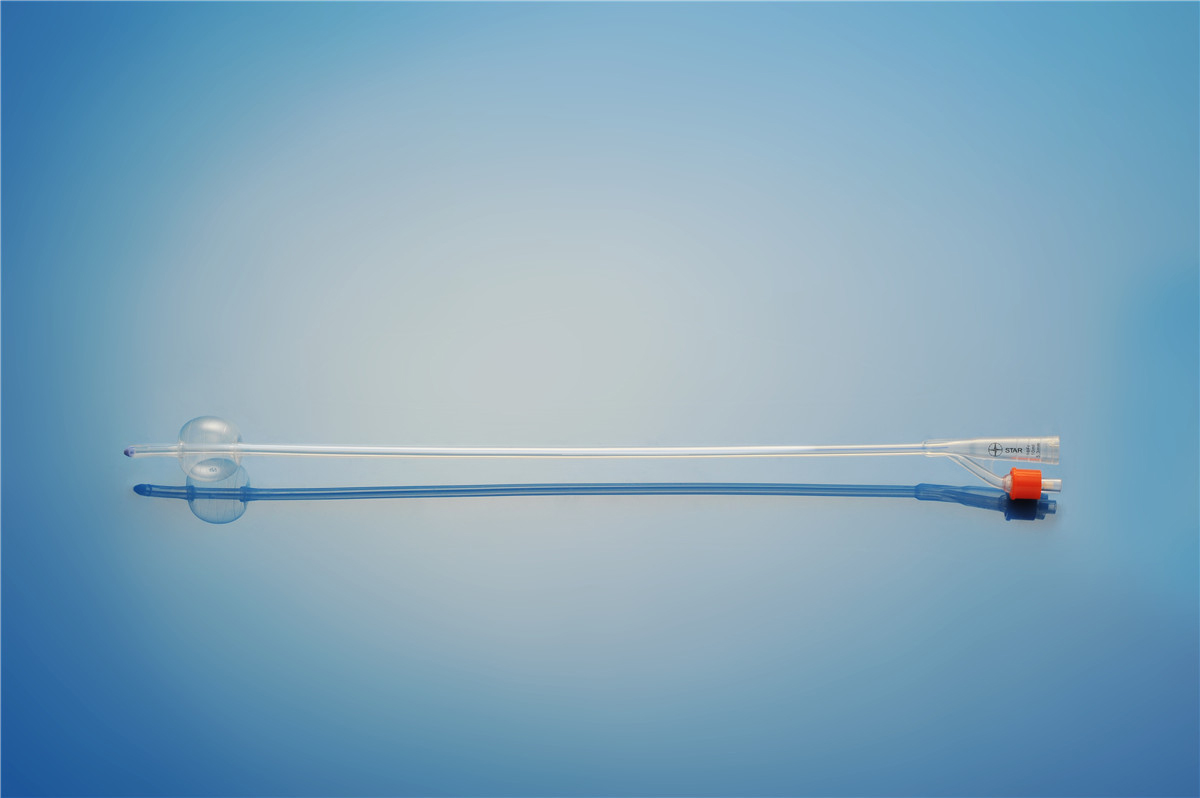

【產品名稱】一次性使用無菌導尿管(取樣型導尿管雙腔兒童型) 【型號】雙腔氣囊取樣型 【規格】:8FR-10FR 【主要結構���、性能】由膠乳為主要原材料制成,可配卡片�。

型號:雙腔氣囊兒童用規格:雙腔氣囊兒童用:8Fr(3mL)���、10Fr(3-5mL)�;結構及組成/主要組成成分:產品由導尿管����、水潤滑包(選配)組成���。雙腔由球囊腔充起錐形接口、排液腔錐形接口����、閥門、管身����、球囊、排液孔組成(尖端有普通尖頭和彎頭區分)����。水潤滑包由無菌水和水刺紗布組成,為輻照滅菌�。導尿管采用天然乳膠和親水潤滑涂...